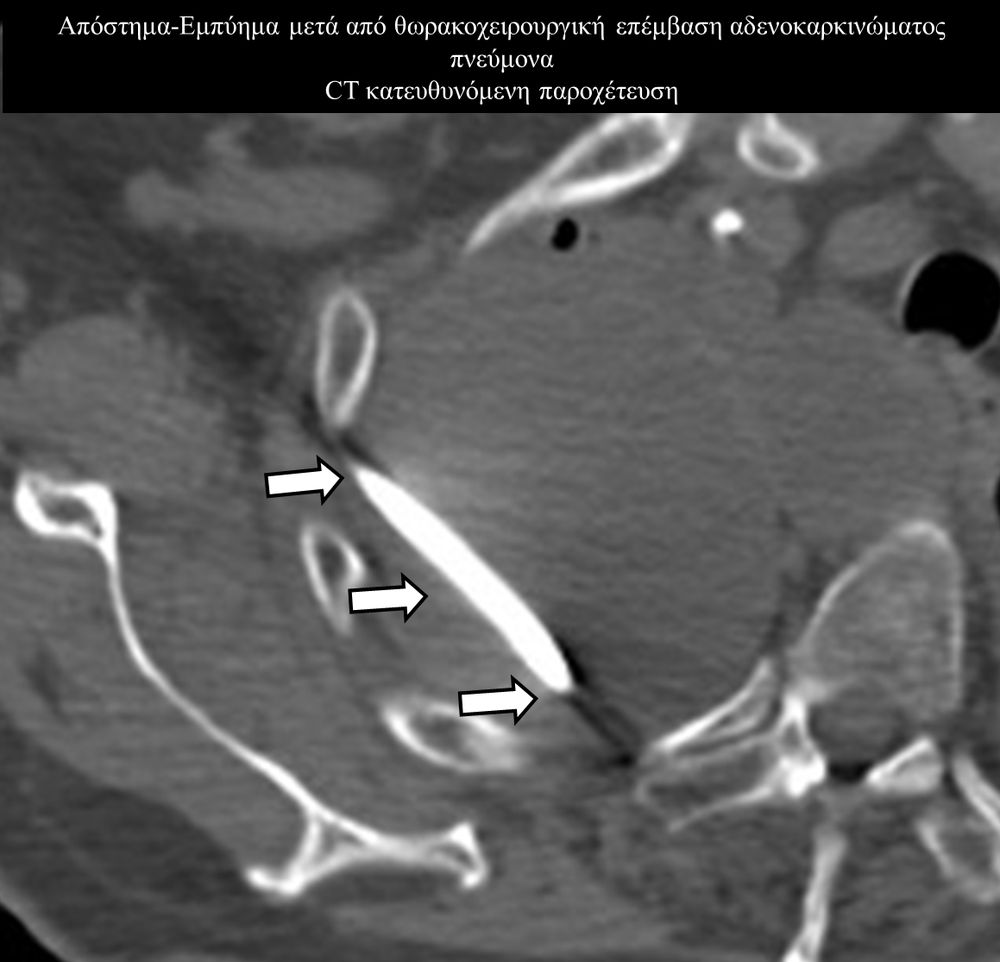

Οι απεικονιστικά καθοδηγούμενες διαδερμικές παροχετεύσεις είναι ελάχιστα επεμβατικές μέθοδοι εξωτερικής παροχέτευσης συμπτωματικών συλλογών, όπως ασκιτικές-καρκινικές-μετεγχειρητικές συλλογές, αποστήματα, πλευριτικές συλλογές-εμπυήματα.

Η παρέμβαση διενεργείται υπό την καθοδήγηση αξονικού τομογράφου ή υπερήχων ή και με συνδυασμό τους. Ο επεμβατικός ακτινολόγος αρχικά αναισθητοποιεί την ανατομική περιοχή ενδιαφέροντος με τη χρήση τοπικής αναισθησίας και παρακεντεί την συλλογή διαδερμικά με λεπτή βελόνη. Στη συνέχεια μέσω ομοαξονικών συστημάτων συρμάτων-καθετήρων-διαστολέωντοποθετείται διαδερμικός καθετήρας τύπου pig-tail εντός της συλλογής, ο οποίος συνδέεται με εξωτερική παροχέτευση.